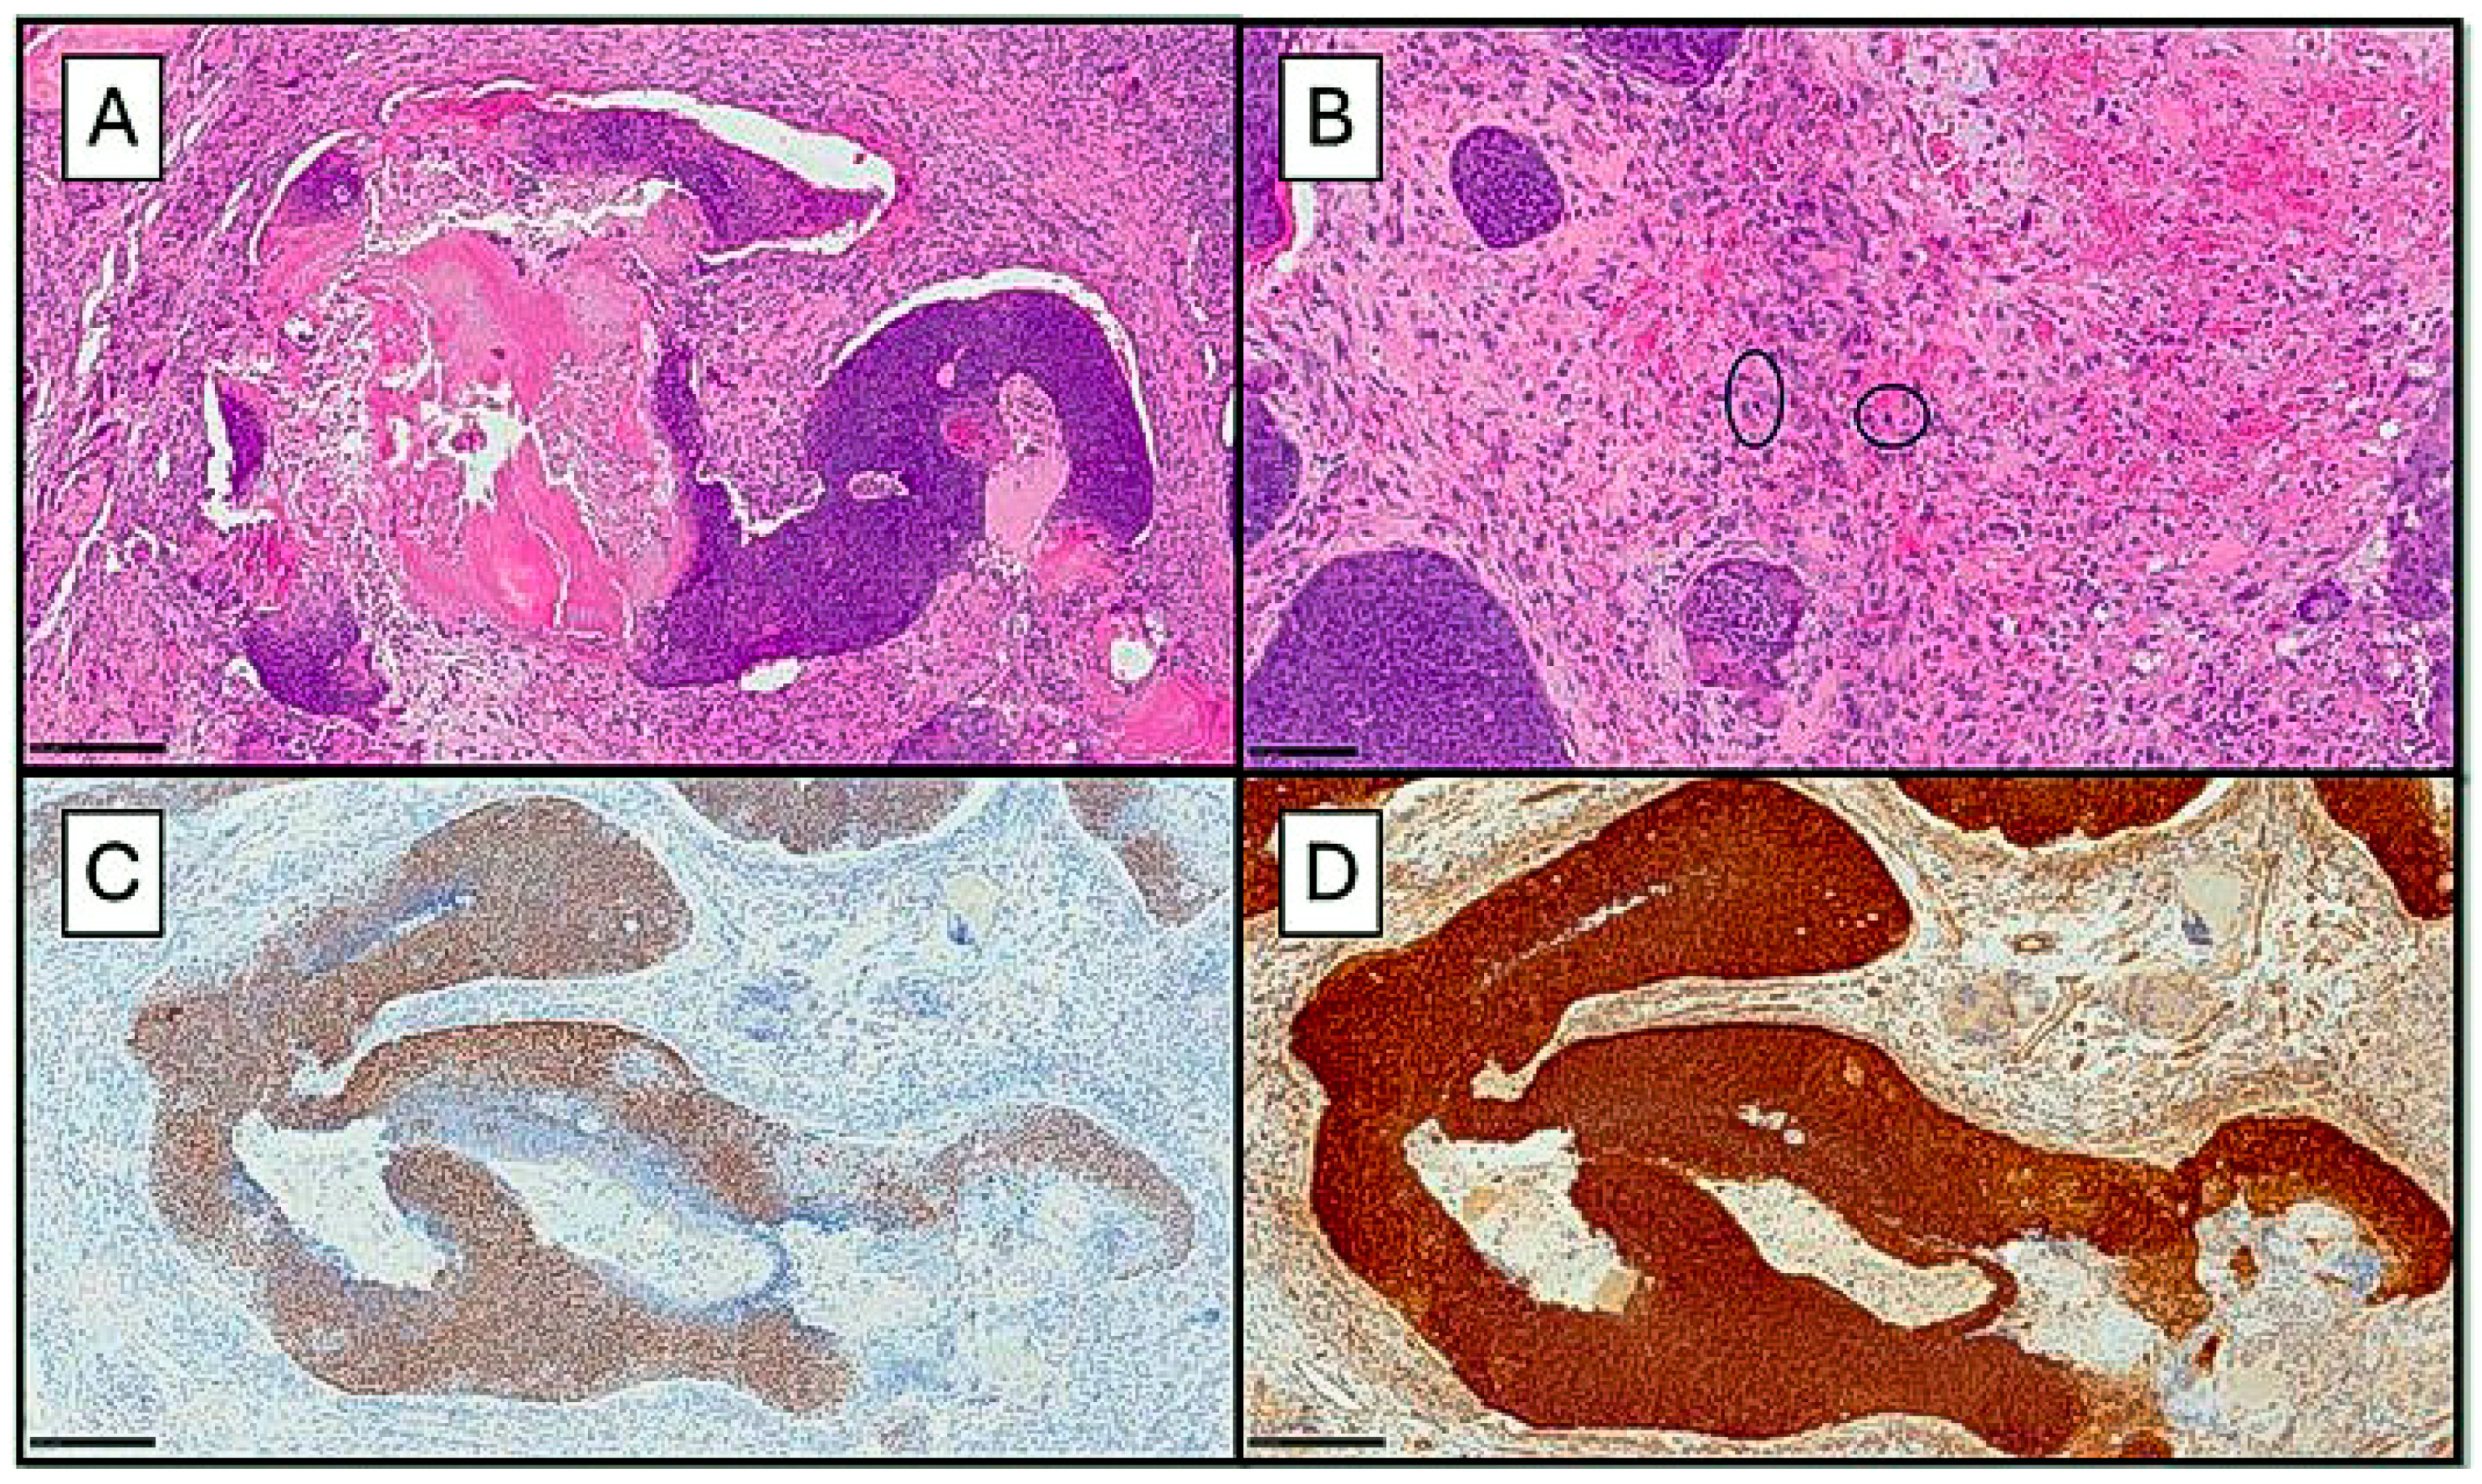

2. Case Presentation

2.1. Case 1

2.2. Case 2

2.3. Case 3